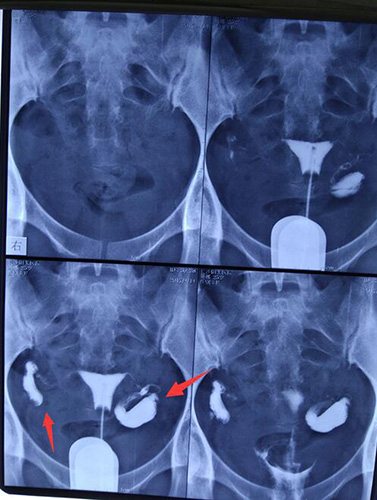

3、给病人注入水性造影剂,在x光下观察并拍片。两次注入造影剂,拍四次片,分别是注入造影剂时、刚注入造影剂时、造影剂完全注入时、造影剂弥散后。

我们来看一个我曾经的患者拍的造影片,她叫*娜,这是在我们医院通过碘海醇造影所拍片的结果,从这张造影片可以看出她的第三、四张拍片中,她的输卵管出现双侧积水,并且左侧的输卵管还有些肿胀,积水情况更为严重。如果在不及时进行治疗疏通输卵管积水,就无法让精卵通过输卵管相遇,成为受精卵,那么她的怀孕几率就很难。